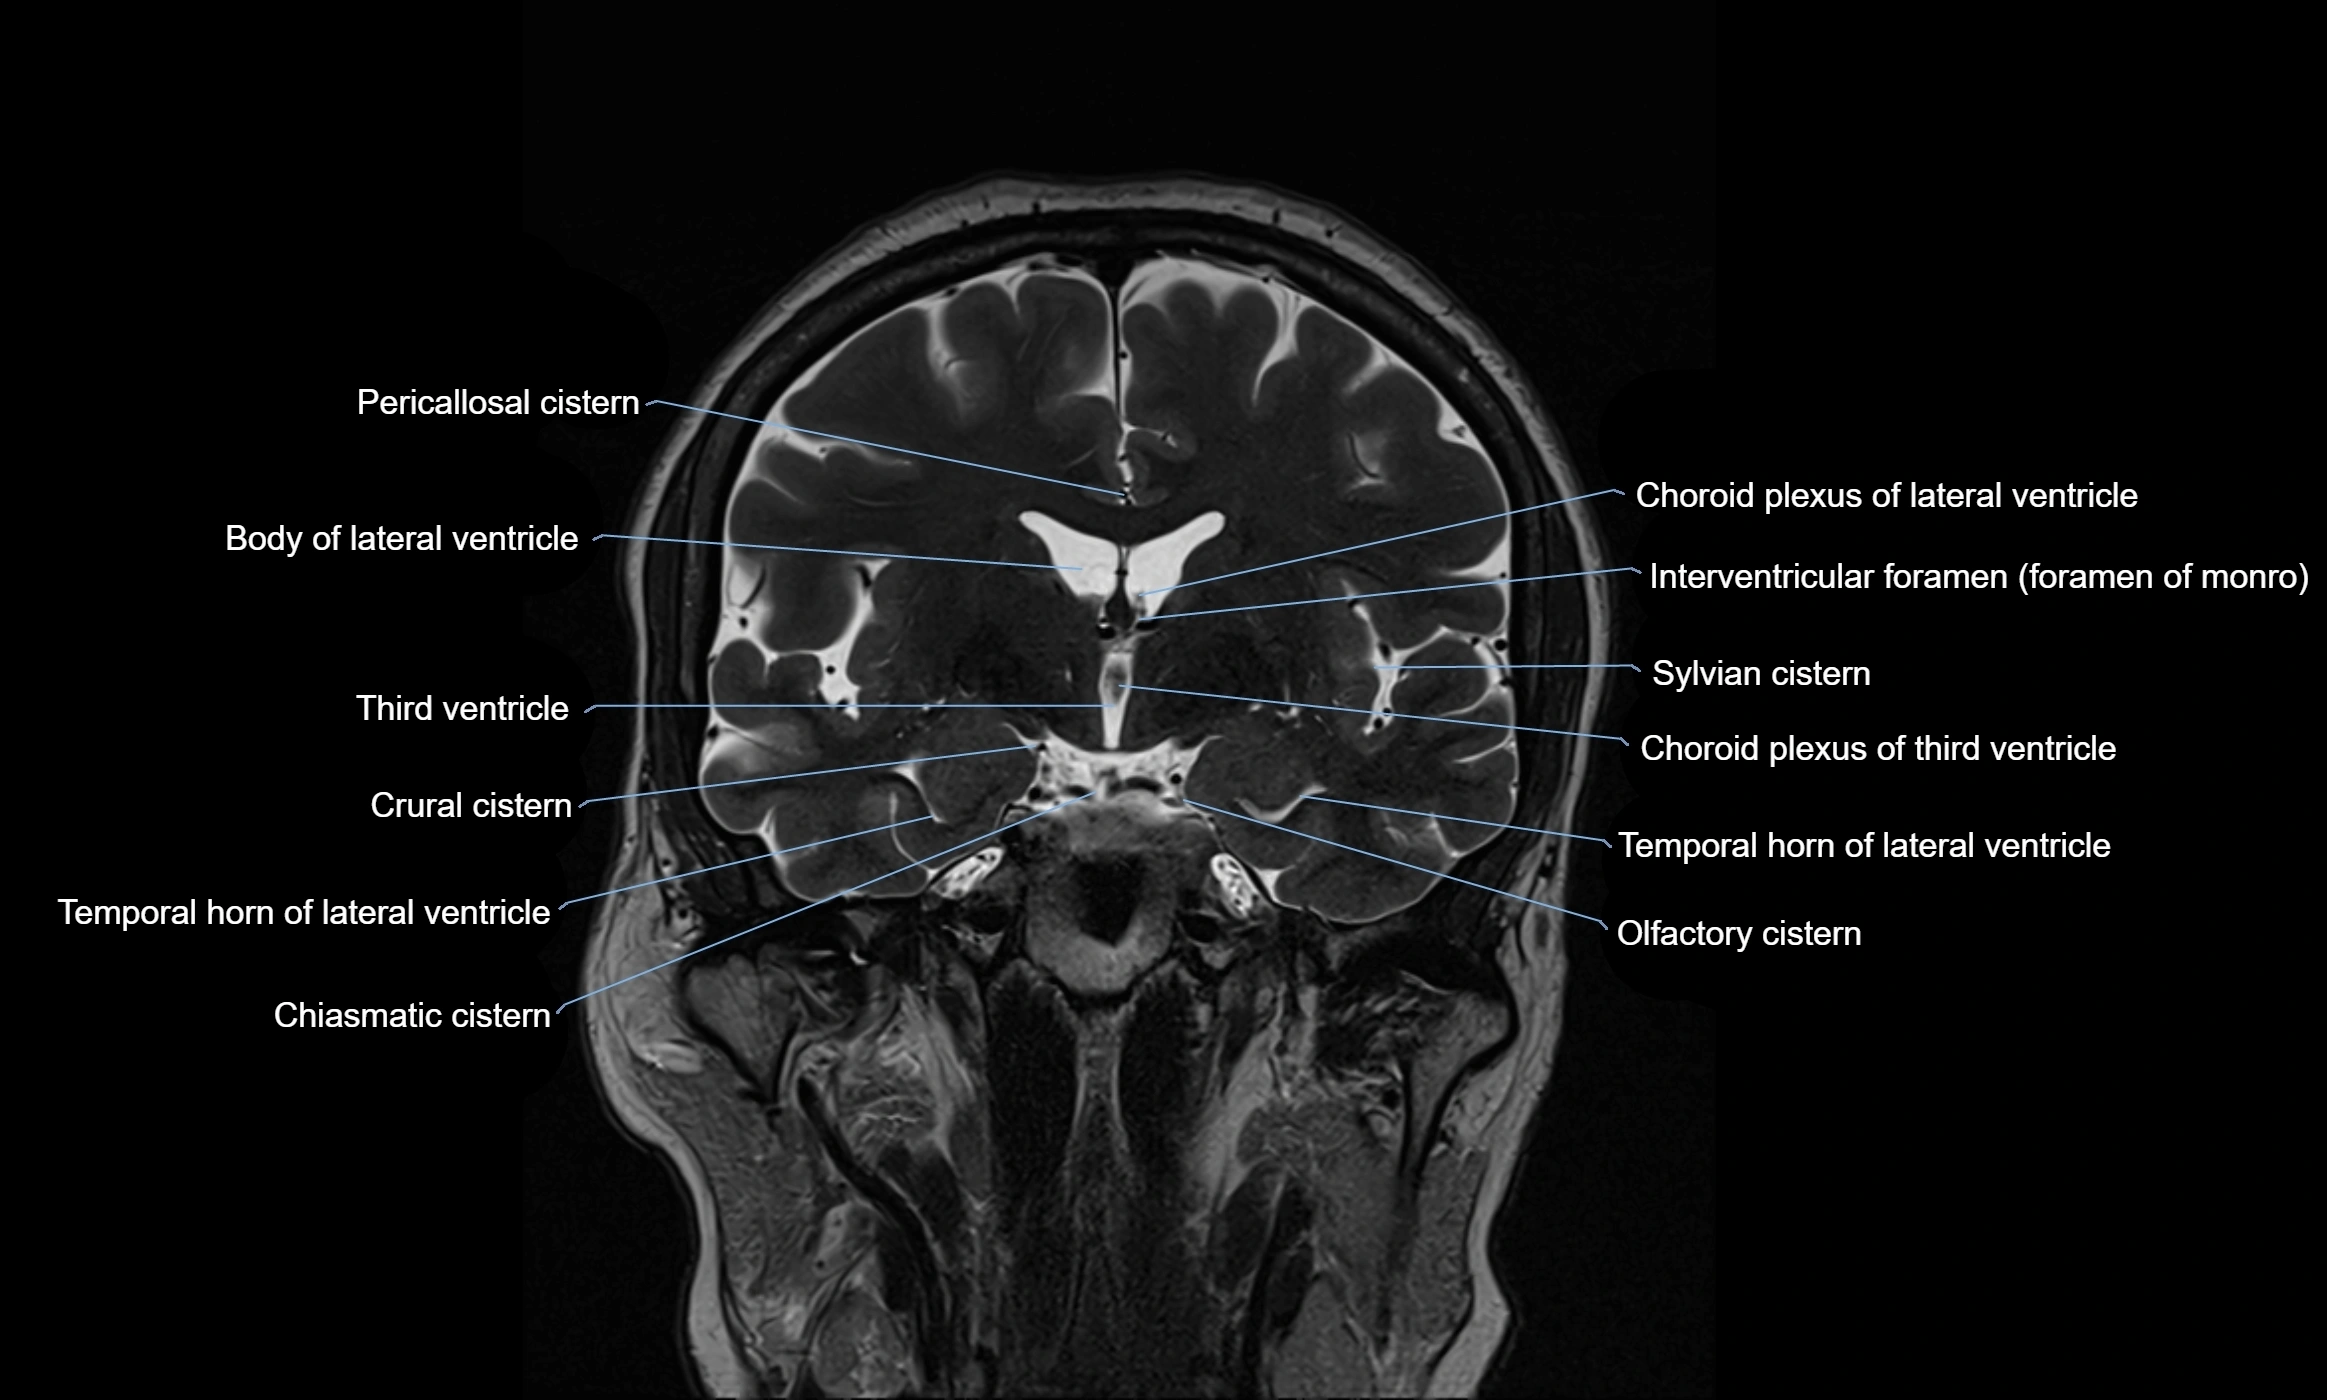

MRI images

image